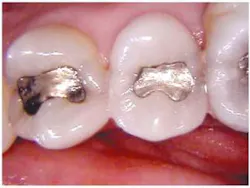

Recurrent caries is difficult to diagnose around an existing amalgam using radiographs. An occlusal DIFOTI image (Fig. 3) will demonstrate recurrent caries around an existing dental restoration.